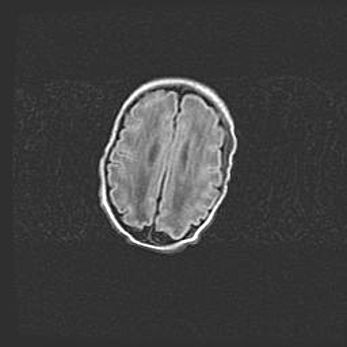

Церебральная ишемия II.

Возраст: 5 дней

Вес: 3400 г

Пол: женский

Окружность головы: 35 см

Срок гестации: 39 недель

Церебральная ишемия – это заболевание, характеризующееся недостаточностью (гипоксией) либо полным прекращением (аноксией) снабжения мозга кислородом по причине закупорки одного или нескольких сосудов. Это приводит к  что метаболическим расстройствам различной степени тяжести в тканях головного мозга, развитию коагуляционных некрозов и гибели нейронов.